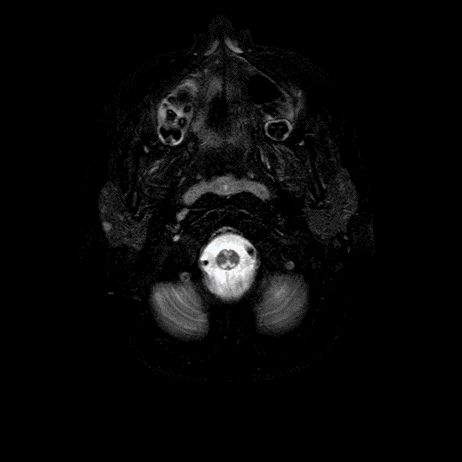

- A) Aksiyel T2A ve koronal T2A sekanslarda sentrum semiovale, korona radiata ve bazal ganglionlar düzeyinde bilateral frontoparietal derin periventriküler beyaz cevherde birleşme eğilimi gösteren hiperintens gliotik sinyal değişiklikleri (oklar) ve aksiyel T2A serilerde servikal spinal kordda posterior kolonda, lateral kesimlerde sinyal artımları (oklar) izlendi.

- LBSL, karakteristik radyolojik özelliklere sahiptir. MRG’de tipik olarak bilateral ve simetrik beyaz cevher sinyal değişiklikleri görülürken, subkortikal U lifleri, internal kapsülün posterior kolları, trigeminal sinir traktları, serebellum, korpus kallozumun spleniumu, medulla oblongata ve omurilikteki dorsal kolonlar ile lateral kortikospinal traktlar genellikle korunur.

- Etkilenen bölgelerde T1’de hipointens, T2/FLAIR’da hiperintens sinyal değişiklikleri izlenir. DWI’de lezyonların periferinde kısıtlı difüzyon görülebilir. MRS’de beyaz cevherde laktat artışı saptanabilir, ancak bu her hastada mevcut değildir.

- LBSL tanısında majör kriterler; subkortikal U lifleri korunmuş serebral beyaz cevher, servikal düzey dahil omurilik dorsal kolonları ve lateral kortikospinal traktlar, medulla oblongata piramitleri veya medial lemniskus dekusasyonu tutulumu iken; minör kriterler korpus kallozum spleniumu, internal kapsül posterior kolu, superior ve inferior serebellar pedinküller, trigeminal sinir traktları, mezensefalik trigeminal yollar, medulla oblongata anterior spinosebellar traktları ve serebellar beyaz cevherdeki sinyal değişiklikleridir.